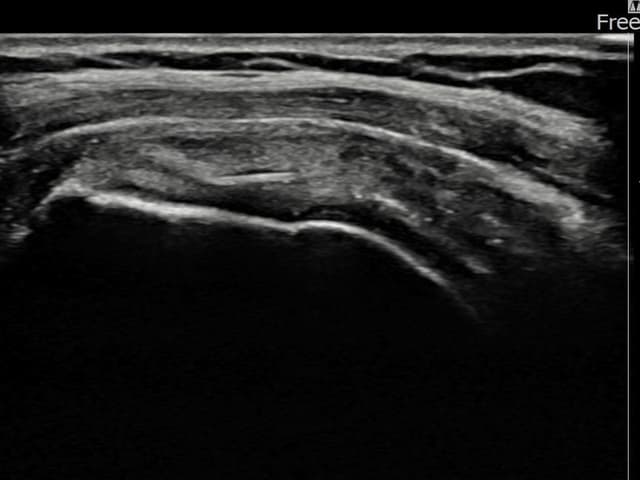

[촬영시기:24.01.25~24.04.03]

[어깨인대 축소봉합술] 좌측 어깨 부착부 통증과 야간 통증으로 수면 장애가 있어 내원하셨습니다.